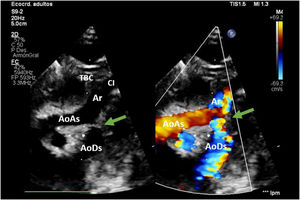

En hipotermia a 33°C se realizó coartectomía con anastomosis término-terminal ampliada; al despinzamiento de la aorta persistía un gradiente de 15mmHg, por lo que se decidió una ampliación del arco distal mediante técnica de Waldhausen invertido, con uso de la arteria subclavia izquierda. No se pudieron completar las anastomosis por la friabilidad de los tejidos, con un tiempo de pinzamiento aórtico acumulado de 68 min (18 min y 50 min en cada procedimiento indicado. respectivamente); se decidió realizar un by-pass parcial izquierdo con la canulación de la aorta torácica descendente (cánula arterial pediátrica A900-98 de 8 Fr, Sorin Group Italia SRL, Mirandola, Italia) y a través del pericardio con un abordaje retro frénico se canuló la aurícula izquierda (cánula DLP maleable 12 Fr, Medtronic, Minneapolis, EE. UU). Una vez asegurada la perfusión tisular total tanto de los troncos supraaórticos como de los órganos dependientes de la aorta descendente, se decidió cambiar de estrategia quirúrgica. Manteniendo el by-pass parcial izquierdo (tiempo de CEC 40 min), se posicionó al paciente en decúbito supino y mediante esternotomía media se procedió a la canulación de aorta ascendente (cánula BioMedicus 10 Fr, Medtronic, Minneapolis, EE. UU.) y aurícula derecha (cánula DLP maleable 12 Fr, Medtronic). Mediante una «Y», el retorno arterial de la CEC perfunde la aorta ascendente (esternotomía) y la aorta descendente (toracotomía izquierda), la cánula de la aurícula izquierda pasa a convertirse en un «vent» (aspirador de cavidades) (fig. 3). Realizamos a continuación un avance de arco aórtico. Se liberó la aorta descendente torácica ampliamente para evitar tensión en las suturas. Se realizó una incisión longitudinal en la aorta ascendente en la proximidad del arco aórtico. La aorta descendente se anastomosó en el arco aórtico proximal. El procedimiento se realizó con parada cardiocirculatoria (36 min) en hipotermia profunda (18°C), con un tiempo acumulado de CEC de 280 min, logrando una reparación completa sin presencia de gradientes residuales (hallazgo que fue corroborado mediante la ecocardiografía postoperatoria de control (fig. 4). Al alta no presentó lesiones neurológicas ni abdominales.

Muestra el abordaje de la esternotomía media (AoAS muestra la cánula de la aorta ascendente; AD la cánula de la aurícula derecha) y la toracotomía postero-lateral izquierda (AoDs la cánula de la aorta descendente; AI la cánula de la aurícula izquierda). Nótese las conexiones en «Y» de las cánulas arteriales (aorta ascendente y descendente) y de las cánulas venosas (aurícula derecha e izquierda).

Ca: caudal; Cr: craneal; D: derecha del paciente; I: izquierda del paciente.